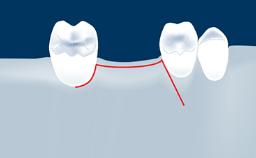

This learning module will provide an overview of the most commonly seen intraoperative and postoperative complications associated with sinus floor elevation and will discuss management in terms of preventative measures as well as treatment strategies.

• intraoperative complications of lateral window sinus floor elevation

• intraoperative complications of transcrestal sinus floor elevation

• postoperative complications of sinus floor elevation